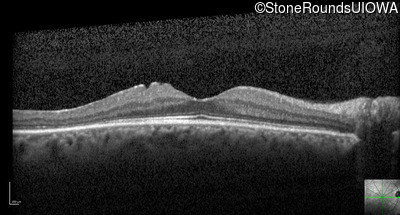

Optical Coherence Tomography - Right - 20/16

Exemplar / OCT Stack

OCT Stack